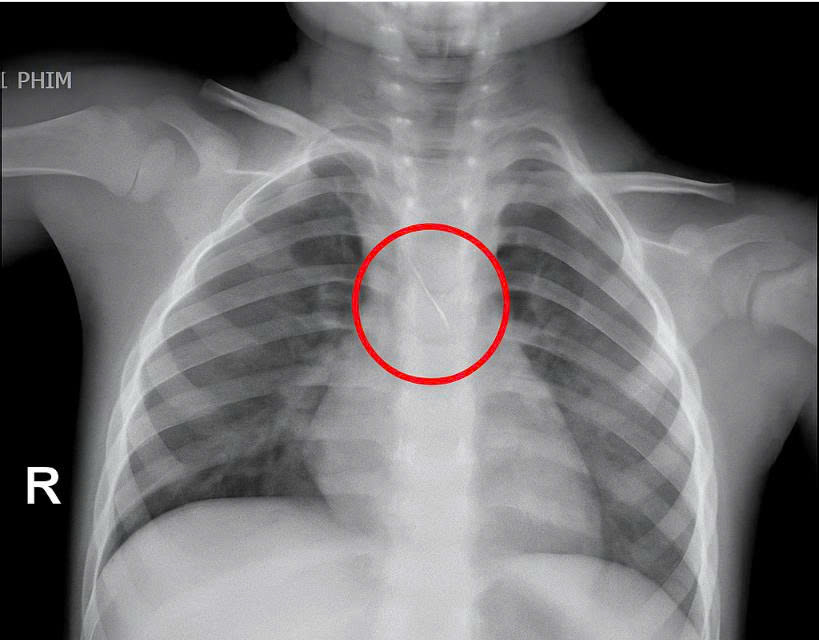

Dị vật trong đường thở cháu bé.

Trước đó, bé nhập viện trong tình trạng ho nhiều, ho sặc. Qua thăm khám và chụp phim, các bác sĩ xác định bé bị sặc kim chọc tủy dài khoảng 22mm, vị trí mắc tại góc carina, nơi chia đôi khí quản. Đây được đánh giá là ca cấp cứu nguy hiểm.